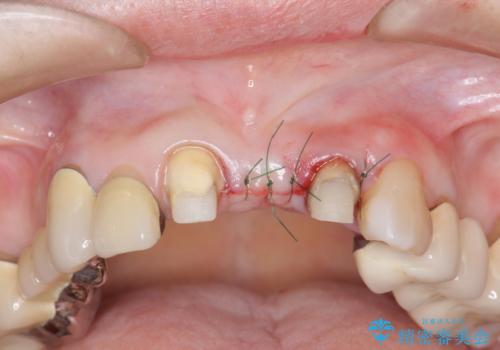

歯肉縁下カリエスも認められるため、挺出を行いセラミックブリッジを審美的に新製します。

虫歯が深くなった場合、挺出や歯周外科を行い歯周組織の状態を改善することでより安定した状態で予知性の高いセラミックブリッジを製作することが可能となります。